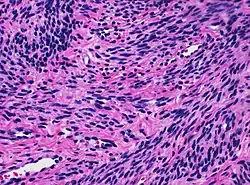

![]() Histology of myometrium | |

The myometrium is the middle layer of the uterine wall, consisting mainly of uterine smooth muscle cells (also called uterine myocytes[1]) but also of supporting stromal and vascular tissue.[2] Its main function is to induce uterine contractions.

The myometrium is located between the endometrium (the inner layer of the uterine wall) and the serosa or perimetrium (the outer uterine layer).

The inner one-third of the myometrium (termed the junctional or sub-endometrial layer) appears to be derived from the Müllerian duct, while the outer, more predominant layer of the myometrium appears to originate from non-Müllerian tissue and is the major contractile tissue during parturition and abortion.[1] The junctional layer appears to function like a circular muscle layer, capable of peristaltic and anti-peristaltic activity, equivalent to the muscular layer of the intestines.[1]

Muscular structure

The molecular structure of the smooth muscle of myometrium is very similar to that of smooth muscle in other sites of the body, with myosin and actin being the predominant proteins.[1] In uterine smooth muscle, there is approximately 6-fold more actin than myosin.[1] A shift in the myosin expression of the uterine smooth muscle may be responsible for changes in the directions of uterine contractions during the menstrual cycle.[1]